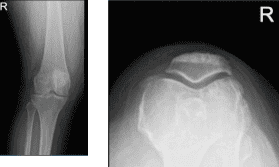

She presented her Xray results, for her left knee there are mild osteoarthritic degenerative changes. For the right knee, there are moderate osteoarthritic degenerative changes. There are no fractures and there are no acute fractures.

Right knee X-ray